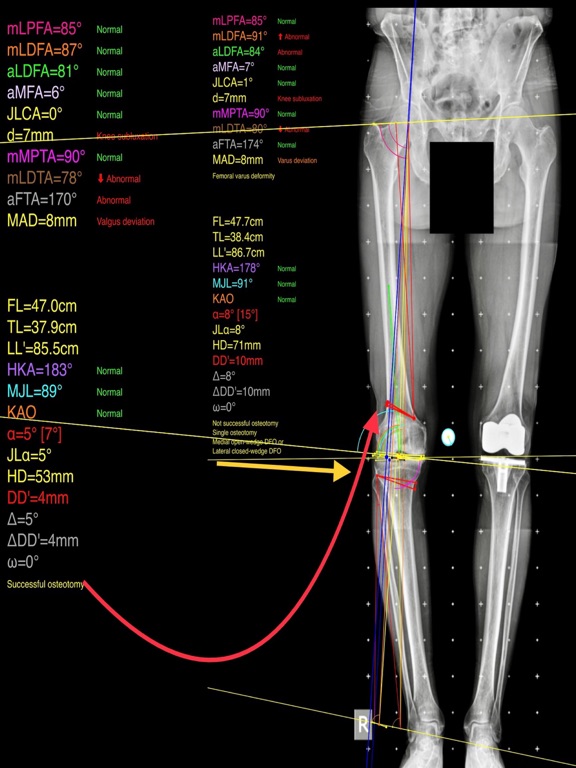

Mal alignment of the hip, knee, and ankle leads to premature cartilage damage and to development of degenerative arthritis of knee joint. Femoral and tibial osteotomies around the knee are established procedures for the restoration of the physiological load distribution of pressure at the knee joint. Accurate preoperative planning is mandatory to avoid under correction or overcorrection of axes or placing the joint-line in obliquity that ends to insufficient postoperative alignment.The majority of osteotomies are still planned and performed using conventional techniques drawing over transparent papers, cumbersome measurements etc.

-mechanical axis deviation (in mm) MAD, anatomical and mechanical femoral axes angle (aMFA),mechanical lateral proximal femoral angle (mLPFA), mechanical lateral distal femoral angle(mLDFA), joint line convergence angle (JLCA),mechanical medial proximal tibial angle (mMPTA), Mechanical lateral distal tibial angle (mLDTA), Hip Knee Ankle line (HKA) ,Mid joint line (MJL) orientation.

-objectively the deviation or deformity in the frontal plane (varus or valgus) and differentiate the level of deformity (femoral and or tibial origin) and according to measured angles objectively suggest where indicated, medial or lateral, open or closed-wedge distal femur osteotomy or high-tibial osteotomy or double osteotomies  and avoiding unwanted obliquity of the joint line

-change the planned mechanical axis to pass at the preferred percentage (Fujisawa point) after evaluation of the residual cartilage thickness left on the involved compartment.

-evaluate in real time the success of intended osteotomy by evaluating the kinematic alignment of the knee (KAO), avoiding residual joint obliquity or malalignment.

-pressing + or - button, one degree of correction is added or subtracted respectively and the second plane of osteotomy emerges and printed in screen real offering real time simulation of the wedge osteotomy in an instant to comprehend in real time what parameters are affected and modify favourably the correction angle. All above mentioned angles and all limp axes are redrawn and updated accordingly for the given new correction angle. The drawn schematic gives the impression of settings  act as a whole interchangable interacting unit.